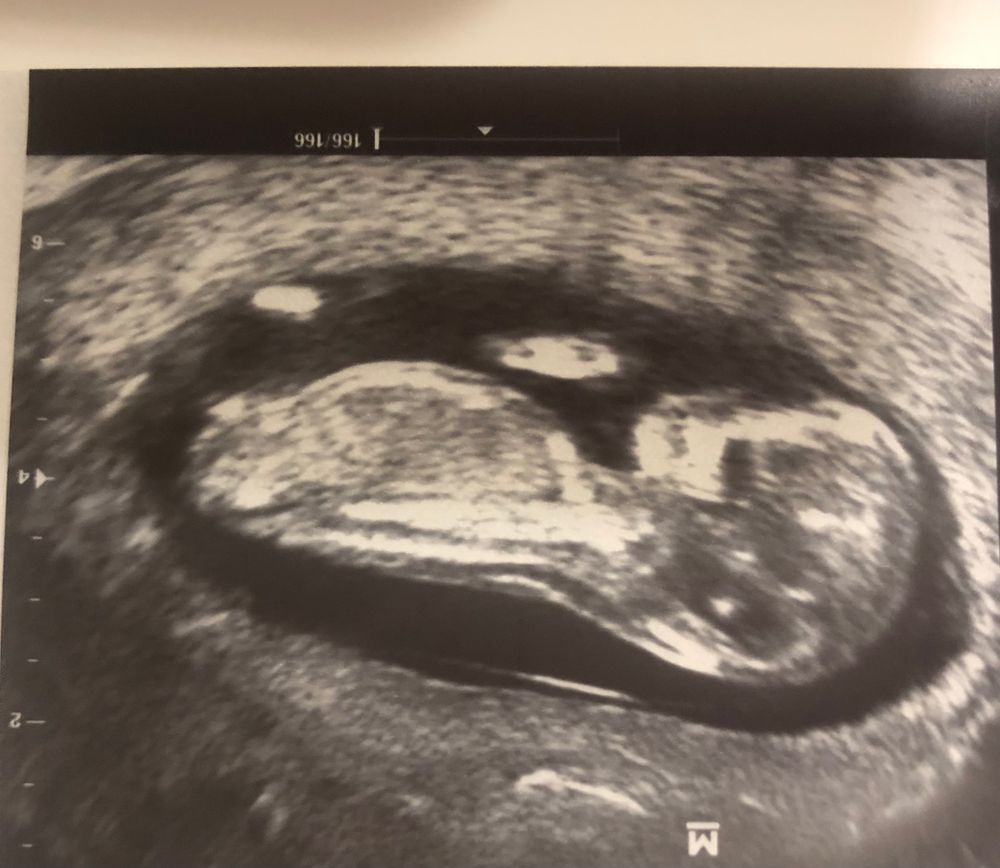

Пол 12.1) погадаем ?

Оля, у вас на девочку похоже

Анализ определение пола Рассказали о нашей доче 🥹💞